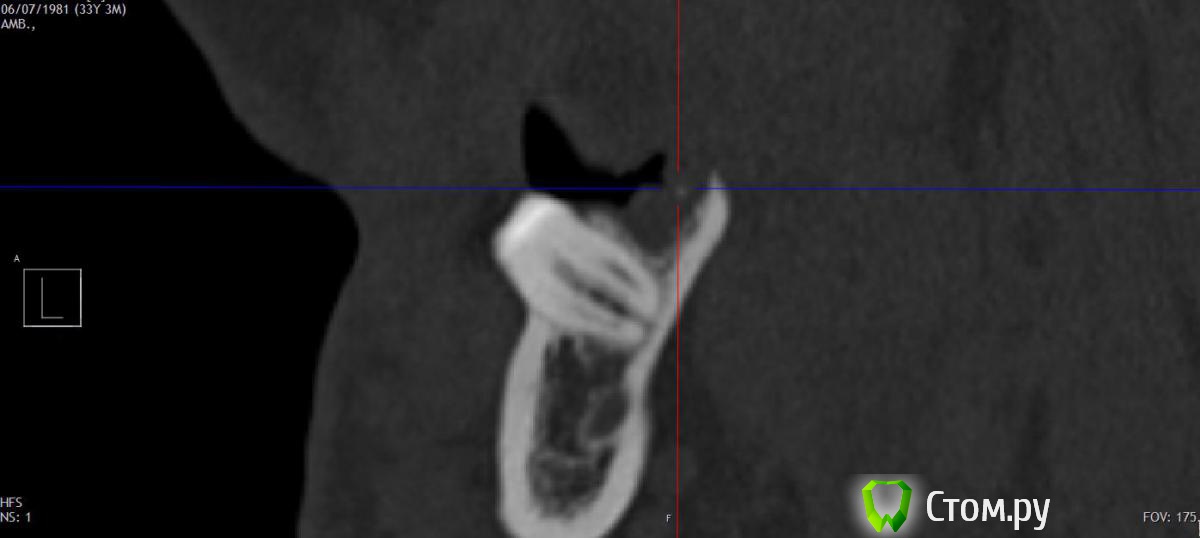

zepo Опубликовано 23 октября, 2014 Автор Поделиться Опубликовано 23 октября, 2014 Сама лунка С суставами все нормально. Ни артроза, ни артрита. Доктор Краснов, я только сейчас понял что вы приложили скриншот лунки 18 зуба.Проблема у меня после удаления 48 зуба, болит уже два месяца и сейчас вот болит.Я покрутил снимки и вот что то нашел. Это не может быть осколком? Ссылка на комментарий

dr-krasnov Опубликовано 23 октября, 2014 Поделиться Опубликовано 23 октября, 2014 Может быть небольшой фрагмент да, для осколка мелковат . . .По поводу сустава, для исключения патологии следует делать не КТ а МРТ и искать того, кто в этом понимает. Ссылка на комментарий

dr-krasnov Опубликовано 23 октября, 2014 Поделиться Опубликовано 23 октября, 2014 http://s020.radikal.ru/i703/1410/82/b2e5265b9dbc.png Лунка 48. Ссылка на комментарий

zepo Опубликовано 23 октября, 2014 Автор Поделиться Опубликовано 23 октября, 2014 http://s020.radikal.ru/i703/1410/82/b2e5265b9dbc.png Лунка 48. Скажите что это??Мои два скриншота тоже 48. Я так понимаю там что то не в порядке? Ссылка на комментарий

red_butler Опубликовано 23 октября, 2014 Поделиться Опубликовано 23 октября, 2014 Я так понимаю там что то не в порядке? на снимке проблем в области 4.8 не вижу Ссылка на комментарий